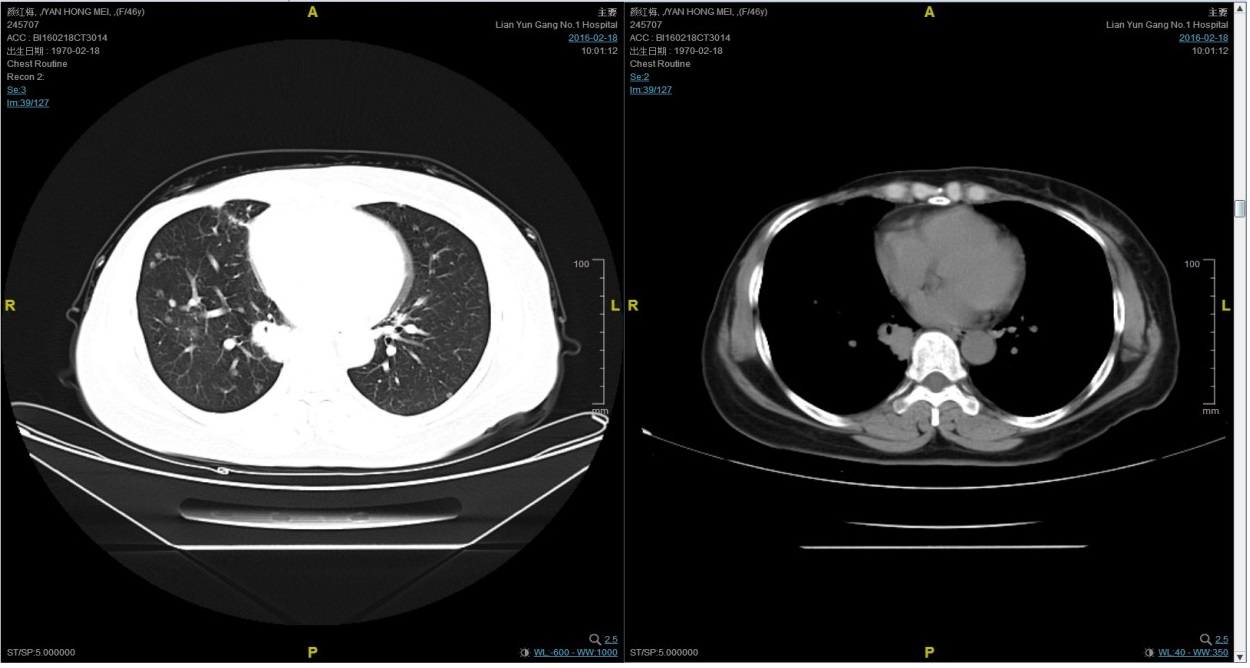

期间2016-4-22复查CT如下:

2016-7-5化疗结束后复查CT,疗效评价稳定。

患者颜X X,女,发病年龄43岁。2010.12.01因体检发现右乳质硬、无痛性肿块住院治疗。入院查体肿块约2.5cm × 1.5cm。考虑诊断为右侧乳腺癌。2010.12.06在我院全麻下“右乳癌改良根治术”。术后病理:(右)乳腺浸润性导管癌,组织学分级Ⅲ级;乳头、皮肤未见癌累及,同侧腋窝淋巴结转移(19/19)。免疫组化:ER(-),PR(-),C- erbB-2(3+)。术后诊断右乳浸润性导管癌并右侧腋窝淋巴结转移(pT2N3M0,IIIC期,HER2阳性型)。术后于2011-01-06起在连云港市第一人民医院给予AC方案化疗4周期,2011-03-20给予右胸壁+右锁骨上下淋巴引流区放疗Dt50Gy/25f,2011-05-26予TH方案化疗4周期(曲妥珠单抗d1首次480mg,以后360mg)共4周期。后续予以曲妥珠单抗360mg(每21天为一周期)维持治疗1年,末次使用曲妥珠单抗的时间在2012年5月,后定期随访,病情稳定。2013-11-23全面复查发现肺转移。 DFS=35个月。2013-11-26起给予曲妥珠单抗(440mg d1)/脂质体紫杉醇(240mg d2)/CBP(500mg d2)方案化疗一个周期,出现Ⅱ度骨髓抑制,因患者主诉乏力明显,后修改方案曲妥珠单抗(330mg 每 3周重复)/脂质体紫杉醇(120mg d1+d8+d15,每4周重复)化疗,化疗过程顺利,患者无明显骨髓抑制,无乏力主诉,于2014-02-11全面复查,疗效评价为PR。继续曲妥珠单抗+脂质体紫杉醇(共六周期)治疗,疗效评价CR。后续予以曲妥珠单抗维持治疗,随访病情稳定。2015年4月,患者肺部病灶复发。给予曲妥珠单抗+希罗达治疗(希罗达1500mg,一天两次口服)。PFS1=17个月。2016-2-18,肺部病灶进展,肺内转移病灶增多。PFS2=10个月。从2016-2-19开始给予紫杉醇+曲妥珠单抗治疗,紫杉醇240mg,3周重复,曲妥珠单抗330mg三周重复。患者末次应用曲妥珠单抗和紫杉醇时间为2016-6-24,紫杉醇共应用4周期。CT评价SD。继续曲妥珠单抗维持治疗,且自服中药。2017-02-27患者因气喘胸闷再次就诊。患者肺部病灶进展,同时出现肝脏转移。再次给予曲妥珠单抗+长春瑞滨化疗一周期,效果不佳,患者放弃治疗。PFS3=12个月。